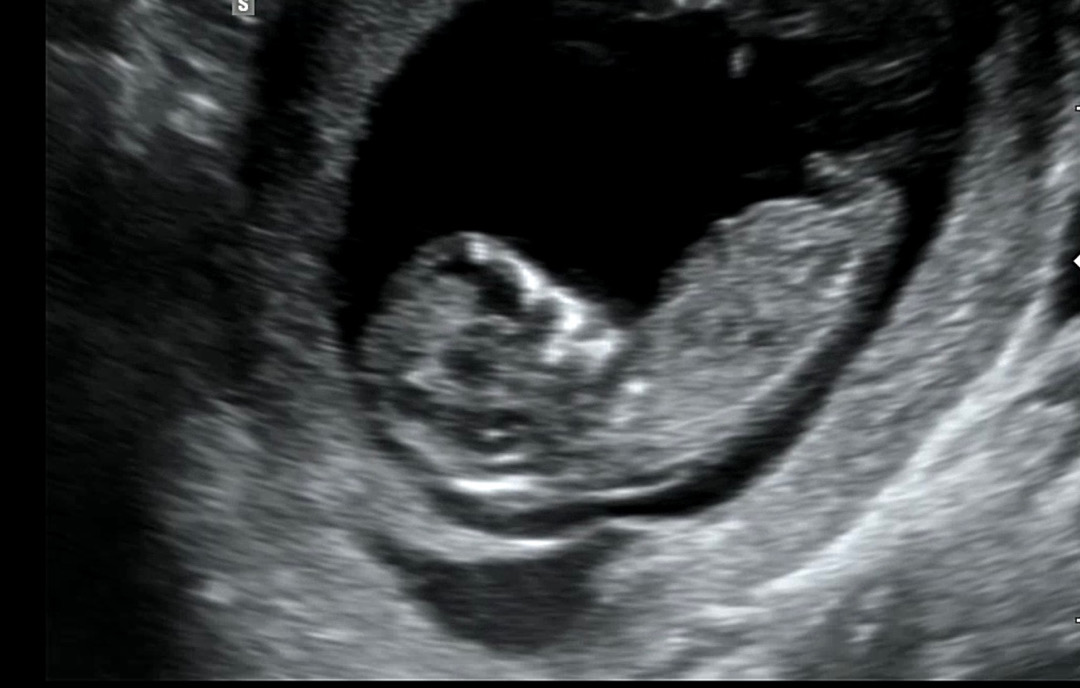

12주0일 각도법 불가능한가요~??ㅠㅠ

요사진 불가한가용 ㅠㅠ 한번만봐주세요~~